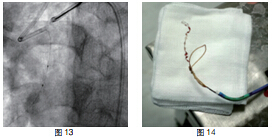

患者RCA为完全闭塞病变,用6F.EBU 3.5导引导管经股动脉对侧造影显示间隔支到RCA远端的侧枝循环,如正向无法开通右冠状动脉可改逆向开通。用JR6F-4导引导管两条pilot-50导引导丝在微导管支持下,用平行导丝技术通过闭塞病变(图3)。分别用Sprinter 1.5 mm×15 mm和2.5 mm×15 mm球囊扩张后RCA开口出现严重夹层,在RCA近端置入Partner 3.0 mm×36 mm支架(图4)。但支架远端仍有严重狭窄,IVUS证实RCA全程弥漫病变,用原2.5 mm球囊扩张后支架远端后,支架远端出现螺旋夹层。拟通过近端支架置入另一Partner 2.75 mm×36 mm支架,但支架无法通过近端支架,头端卡在第一个支架内,在反复用力推送过程中导引导管、导丝自RCA中脱出、将支架球囊弹出,支架球囊撤出体外后发现支架已脱落。透视RCA开口至桡动脉全程,及导引导管内,未发现脱落支架。迅速将原JR4导引导管到位,置BMW导丝到RCA远端,保证RCA开通(图5),IVUS证实导丝全程在真腔内。用原2.5 mm球囊扩张RCA远端以便器械通过(图6)。血管内超声检查提示RCA中段螺旋夹层,撕裂深及血管外膜(图7)。右冠近端支架膨胀、贴壁良好(图8)。将超声导管回撤至右冠状动脉开口处,可见脱落支架卡在右冠状动脉近端支架开口处(图9)。拟取出支架,为预防取出支架过程中RCA急性闭塞,在RCA远端置入BuMA 2.5 mm×30 mm和3.0 mm×30 mm支架,近端支架和原RCA开口处支架未连接(图10)。将Snare圈套器经原作为对侧造影的6F.EBU 3.5导引导管伸出(图11),调整位置,将脱落的支架套住。同时将RCA内的导丝保留,RCA近端支架内预置一3.0 mm×10 mm高压球囊,以保护在取出脱落支架时RCA开口处支架不受影响(图12)。在回撤圈套器时遇到较大阻力,反复推拉,在取出脱落支架的同时将置入RCA开口已释放的的Partner 3.0 mm×36 mm支架带出(图13~14)。RCA开口出现螺旋夹层,但未闭塞。立刻重新置入导丝,IVUS证实导丝在真腔内,在RCA近端分别置入BuMA3.0 mm×25 mm和3.5 mm×20 mm支架,RCA无残余狭窄,血流TIMI3级(图15)。